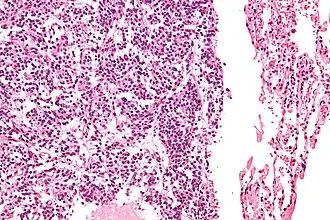

Micrografia de um típico tumor carcinoide pulmonar.

O diagnóstico definitivo é alcançado por um exame microscópico, após excisão. Os tumores carcinoides típicos apresentam células com cromatina pontilhada e uma quantidade moderada de citoplasma. Eles realizam menos mitoses e têm uma baixa necrose. Por definição, eles sã0 maiores do que 4 mm em sua maior dimensão.